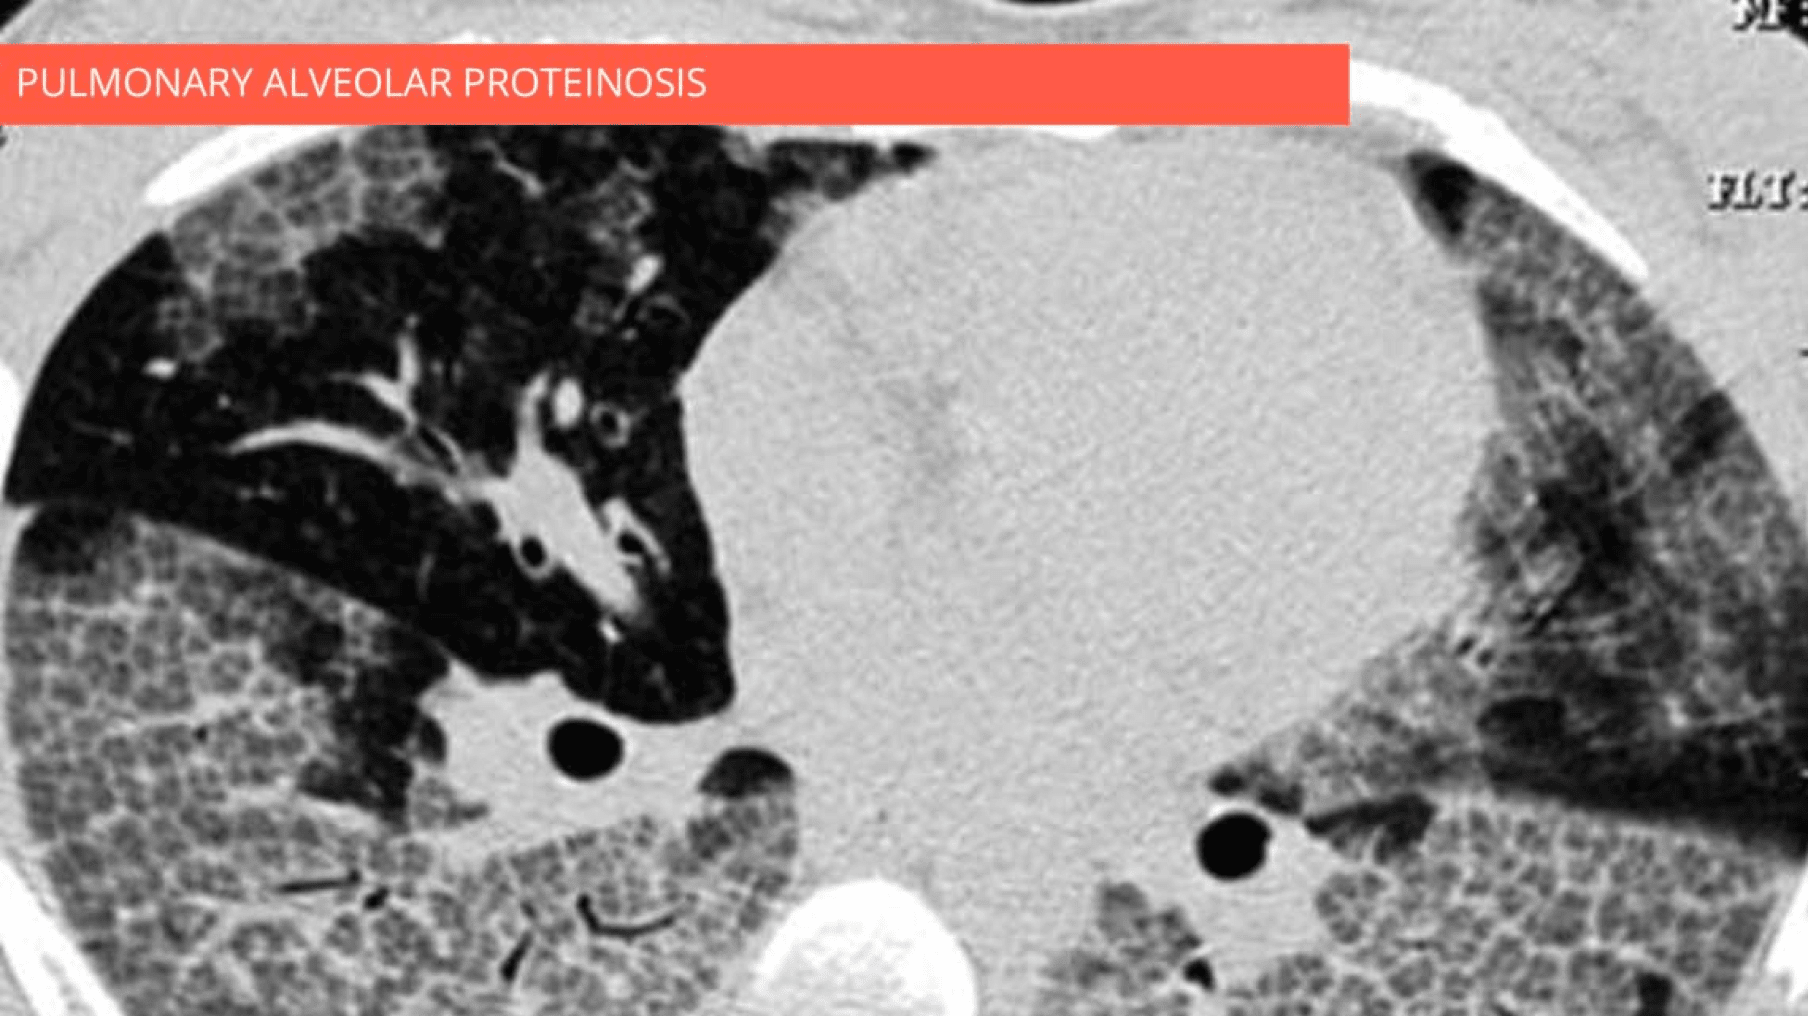

Combination of ground-glass opacity, thickened polygonal septal lines, and intralobular reticulations predominantly in the lower lobes. Note the spatial heterogeneity of lesions.